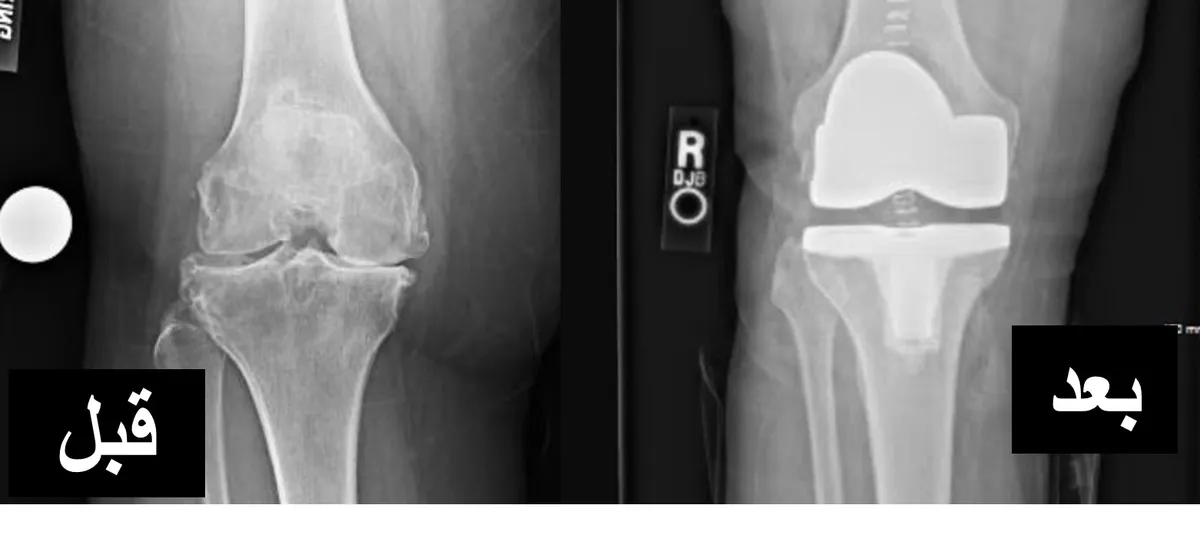

صورة توضيحية: تشريح الركبة والمفصل الصناعي بعد الاستبدال